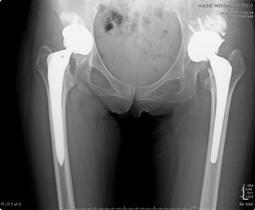

どの術式を選択するか?

(1) 両側骨移植併用

(2) 両側高位設置

(3) 片側骨移植併用